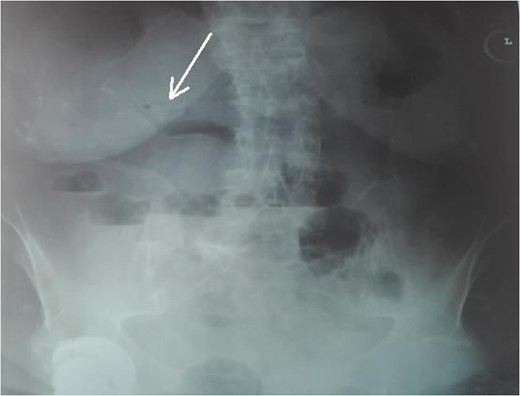

An 87-year-female patient was admitted to emergency department complaining about vomiting for the past 7 days with mild abdominal pain. The patient was hemodynamically stable, had sluggish bowel sounds and soft abdominal wall with mild tenderness. The patient also suffered from atrial fibrillation, heart failure, myelodysplastic syndrome, hiatus hernia and cholelithiasis. The findings of the laboratory tests were unremarkable. Plain chest and abdominal radiograms revealed hiatus hernia with gastric dilation (Fig. 1), a few air-fluid levels and pneumobilia, with delineation of extrahepatic and intrahepatic bile ducts by air (Fig. 2). A nasogastric tube was inserted, which drained biliary content. An abdominal computed tomography (CT) scan revealed the presence of air in the intrahepatic bile ducts, free air and leakage of oral contrast agent in the hepatic hilum and subhepatic space and an impacted gallstone in the third portion of the duodenum (Figs 3 and 4). The diagnosis of cholecystoenteric fistula and proximal gallstone ileus was set.

Chest radiogram. The arrow shows the dilated intrathoracic stomach.